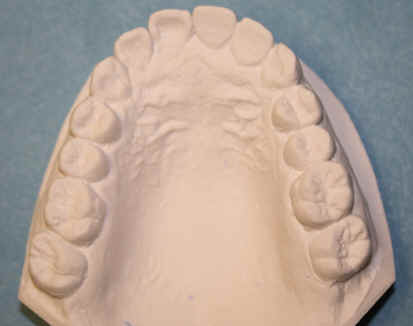

Comprehensive Treatment

23 year-old female, "I want braces"

Dental history: #9 fracture at age of 8; #9,10 crowns (joined) 2 years ago; #9 has chronic apical infection, #19 extracted due to caries at age of 15

#1,16,32 extracted before comprehensive exam, after pan taken